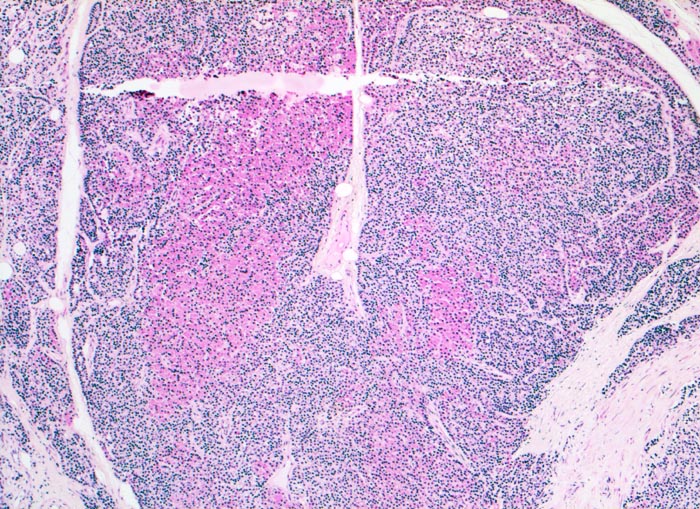

Morphologisch besteht bei sHPT eine Hauptzellhyperplasie. Makroskopisch findet sich eine meist ungleich ausgebildete Vergrösserung aller Nebenschilddrüsen. Die Grösse der Drüsen entspricht der Schwere und der Dauer des Stimulus. Die im früheren Stadium gefundene diffuse Hyperplasie mit Ersatz des Stromas und der Fettzellen durch chronisch stimulierte Hauptzellen (> 558) (> 559) geht im späteren Stadium in eine noduläre Hyperplasie („Pseudoadenome“) über (> 2358). Die regulierte Anpassung der Nebenschilddrüsen kann in eine Autonomie übergehen (tHPT) (> 3704). Morphologisch besteht in diesem Fall eine unregelmässige noduläre Hyperplasie. Gelegentlich entwickelt sich beim tHPT ein dominanter Knoten, der morphologisch nicht von einem Adenom bei pHPT unterscheidbar ist.

• Knotige vergrösserte Nebenschilddrüse. Abgrenzung der einzelnen Knoten durch breite Fibrosebänder.

• Hyperplasie lipidarmer Hauptzellen.

• Areale mit oxyphilen Zellen.

• Verminderter Fettgehalt (<<35%). Für normale Nebenschilddrüsen gilt: